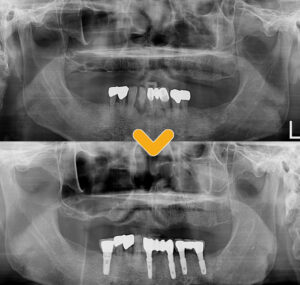

엑스레이 사진을 보시면

노란색의 점선은

현재 환 자분의 잇몸뼈 높이로,

염증으로 인해 잇몸뼈가 소실되어

많이 내려가 있는 모습입니다.

이미 아래쪽 왼쪽과 오른쪽의

큰 어금니들은 상실되었고,

남아있는 치아들도 치료가 필요하였습니다.

아래 앞니 부위에는

뿌리 주위로 까맣게 염증이 보이고,

양쪽의 큰 어금니들이 상실되어

음식을 저작할 때 앞니로만 사용하여

영향이 간 것으로 판단되었는데요.

또한 위쪽은 현재 환자분께서

틀니를 사용하시고 있으셨습니다.

대부분의 치아가

잇몸 상태가 좋지 않았지만

오른쪽 아래 송곳니와 첫 번째 작은어금니,

두 번째 작은 어금니는 살려서 사용하며,

나머지 치아는 보존하기 어렵다고 판단해

발치 후 임플란트를 진행하였습니다.

또한 환자분께서 말씀하신

어금니 또한 저작 기능을 할 수 있도록

임플란트 식립도 함께 진행하였습니다.

수암동치과 전후 차이